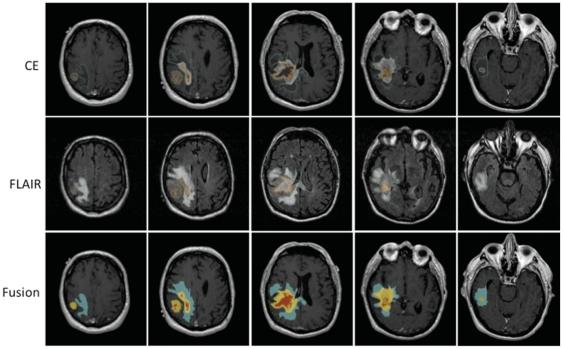

Despite recent discoveries of new molecular targets and pathways, the search for an effective therapy for Glioblastoma Multiforme (GBM) continues. A newly emerged field, radiogenomics, links gene expression profiles with MRI phenotypes. MRI-FLAIR is a noninvasive diagnostic modality and was previously found to correlate with cellular invasion in GBM. Thus, our radiogenomic screen has the potential to reveal novel molecular determinants of invasion. Here, we present the first comprehensive radiogenomic analysis using quantitative MRI volumetrics and large-scale gene- and microRNA expression profiling in GBM.

尽管最近发现了新的分子靶点和途径,但仍在寻找胶质母细胞瘤(GBM)的有效治疗方法。一个新兴的领域,放射基因组学,将基因表达谱与 MRI 表型联系起来。MRI-FLAIR 是一种非侵入性诊断方式,先前发现与 GBM 中的细胞侵袭相关。因此,我们的放射基因组筛选有可能揭示侵袭的新分子决定因素。在这里,我们使用定量 MRI 体积测量和 GBM 的大规模基因和 microRNA 表达谱进行了首次全面的放射基因组分析。